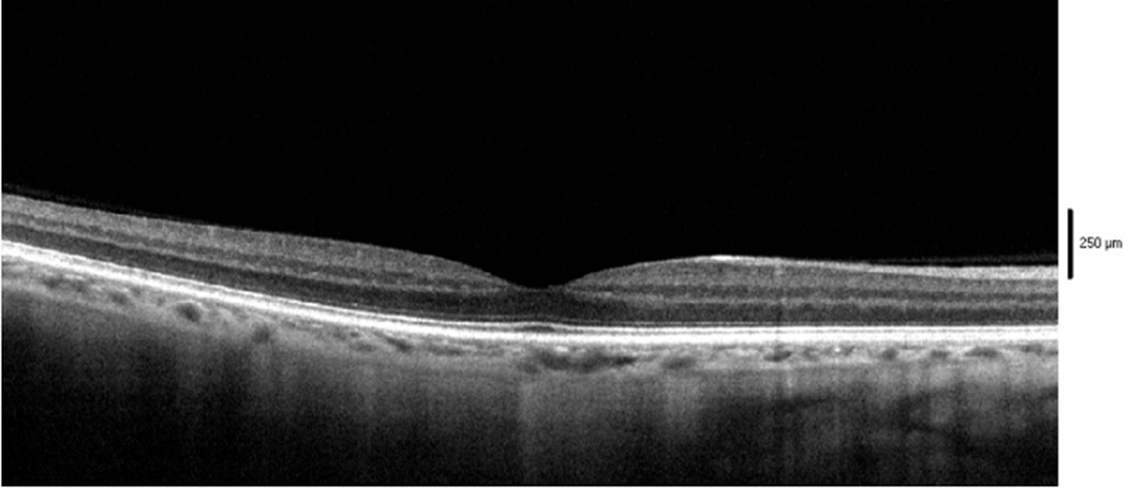

OCT:

La tomografia a coerenza ottica (OCT) è una metodica di imaging retinico non invasiva, non a contatto, che permette lo studio di sezioni retiniche ad alta risoluzione. Si basa sul principio dell'interferometria a bassa coerenza. L'esame, attraverso una luce laser a bassa coerenza, valuta la reflettività dei vari strati retinici in modo da permettere la visualizzazione di eventuali alterazioni patologiche. Le immagini, ottenute secondo i diversi piani di scansione (verticale e orizzontale), consentono uno studio completo della regione maculare e della papilla ottica. I nuovi apparecchi hanno permesso, attraverso una velocità delle scansioni aumentata, la riduzione degli artefatti e un aumento della risoluzione.